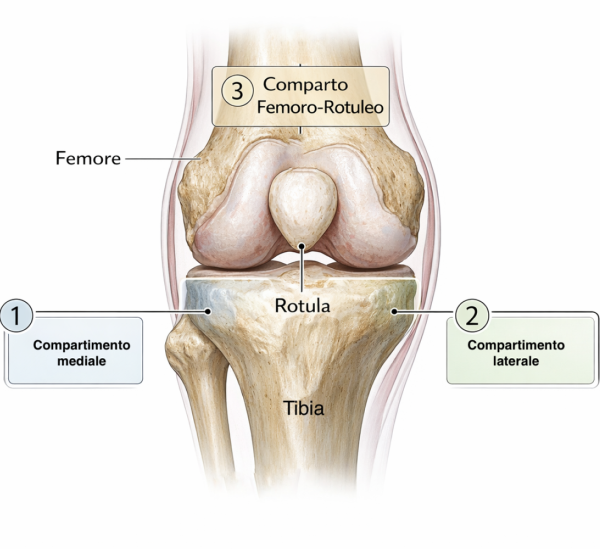

Indicazioni principali

- Artrosi monocompartimentale (mediale o laterale)

Indicazione cardine: osteoartrosi severa confinata a un compartimento (tipicamente “bone-on-bone”) con sintomatologia coerente e fallimento del trattamento conservativo.

UKA mediale vs UKA laterale: differenze pratiche

UKA mediale (AMOA come scenario tipico)

Pattern classico: usura antero-mediale, compartimento laterale preservato, ACL funzionale, deformità in varo correggibile.

UKA laterale

Meno frequente e più “selettiva” per anatomia/biomeccanica, ma con indicazioni ben descritte:

OA laterale moderata-severa con compartimento mediale a cartilagine a tutto spessore, legamenti integri, deformità in valgo correggibile e contrattura limitata (spesso <10–15°). Controindicazioni ricorrenti: artrite infiammatoria e coinvolgimento patello-femorale severo.